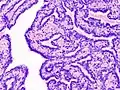

.jpg.webp) Histopathology of intraductal papilloma of the breast by excisional biopsy. Hematoxylin and eosin stain. Histopathology of intraductal papilloma of the breast by excisional biopsy. Hematoxylin and eosin stain.